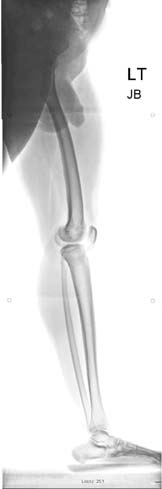

术前站立位EOS扫描X光片。(B) 使用PRECICE 1 10.7毫米胫骨髓内钉进行双侧胫骨延长术。(C) 两周后,取出先前的股骨髓内钉,并植入双侧10.7毫米PRECICE 1转子入口髓内钉。双侧股骨延长6.5厘米,同时胫骨延长5厘米。分期植入髓内钉是为了避免因扩四个骨骼的髓腔而增加脂肪栓塞风险。(D) 患者目前身高为62英寸(158厘米)。)